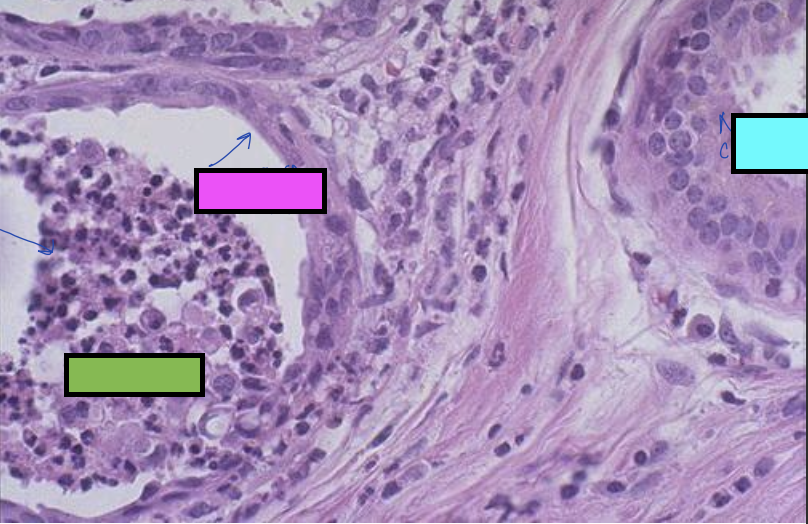

what is the image showing?

squamous metaplasia

what is the blue box cell showing?

normal cuboidal cell of salivary glands

what is the pink box cell showing?

flattened squamous cell from squamous metaplasia

what is the green box cell showing?

blockage of salivary duct